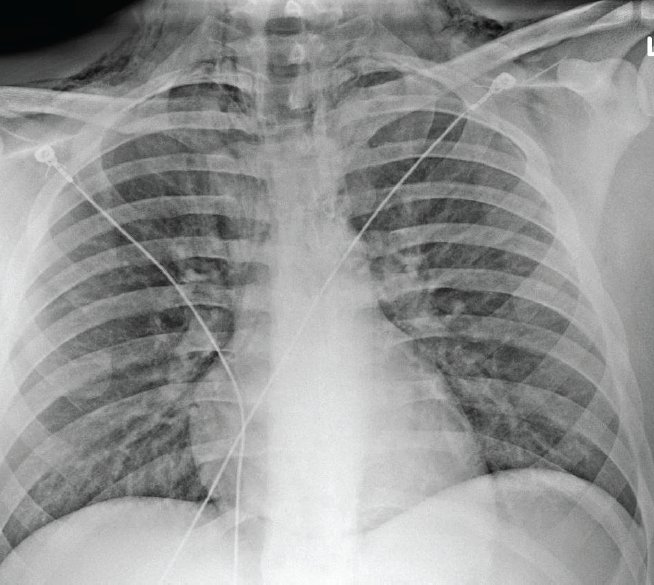

Laboratory evaluation included a normal lipase and complete metabolic panel. A plain radiograph revealed pneumomediastinum (Figure). A fluoroscopic esophagram was negative for signs of esophageal leak.

Reported sequelae of CHS include esophagitis, pneumomediastinum, weight loss, burns/scalding from hot showering, dehydration and Mallory-Weiss tears.2,4,7 Pneumomediastinum was noted in our patient with classic signs during the physical exam, including subcutaneous emphysema and an audible crunch during cardiac auscultation. This extra noise is known as Hamman’s sign and occurs when the heart beats against air-filled mediastinal tissue.